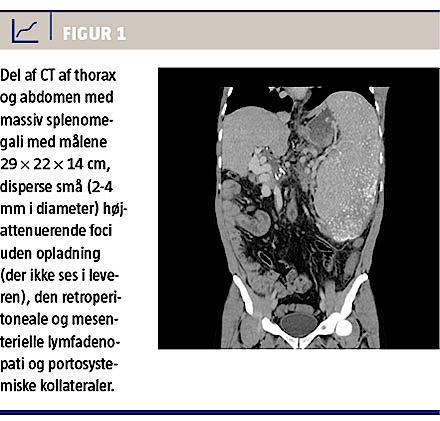

I 1993 blev en dengang 14-årig dreng overflyttet til en medicinsk afdeling fra et længere udredningsforløb i pædiatrisk regi. Symptomerne var træthed, dyspnø og mavesmerter. Ved CT fandt man en monstrøs forstørret milt samt generaliseret forstørrede lymfeknuder i aksiller, thorax og abdomen (Figur 1). I lungerne sås nodulære infiltrater. Bioptisk fandt man granulomer med kæmpeceller, men ingen nekrose. Der var intet holdepunkt for malignt lymfom. Et omfattende undersøgelsesprogram bidrog ikke yderligere til diagnosen.